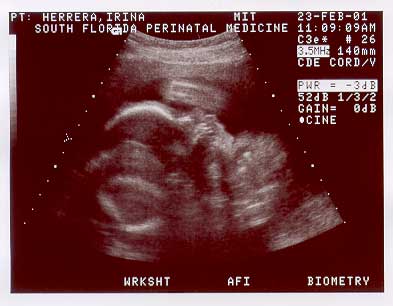

Baby yawning during the ulstrasound!

Week 25:  Baby yawning! Captured during U/S session, Feb. 23, 2001.

Welcome to the second page of Nicolas' u/s images taken on Feb. 23. 2001, at 25 wks.

BABY1-~1.jpg (16639 bytes)

Image sequence 4 of 6